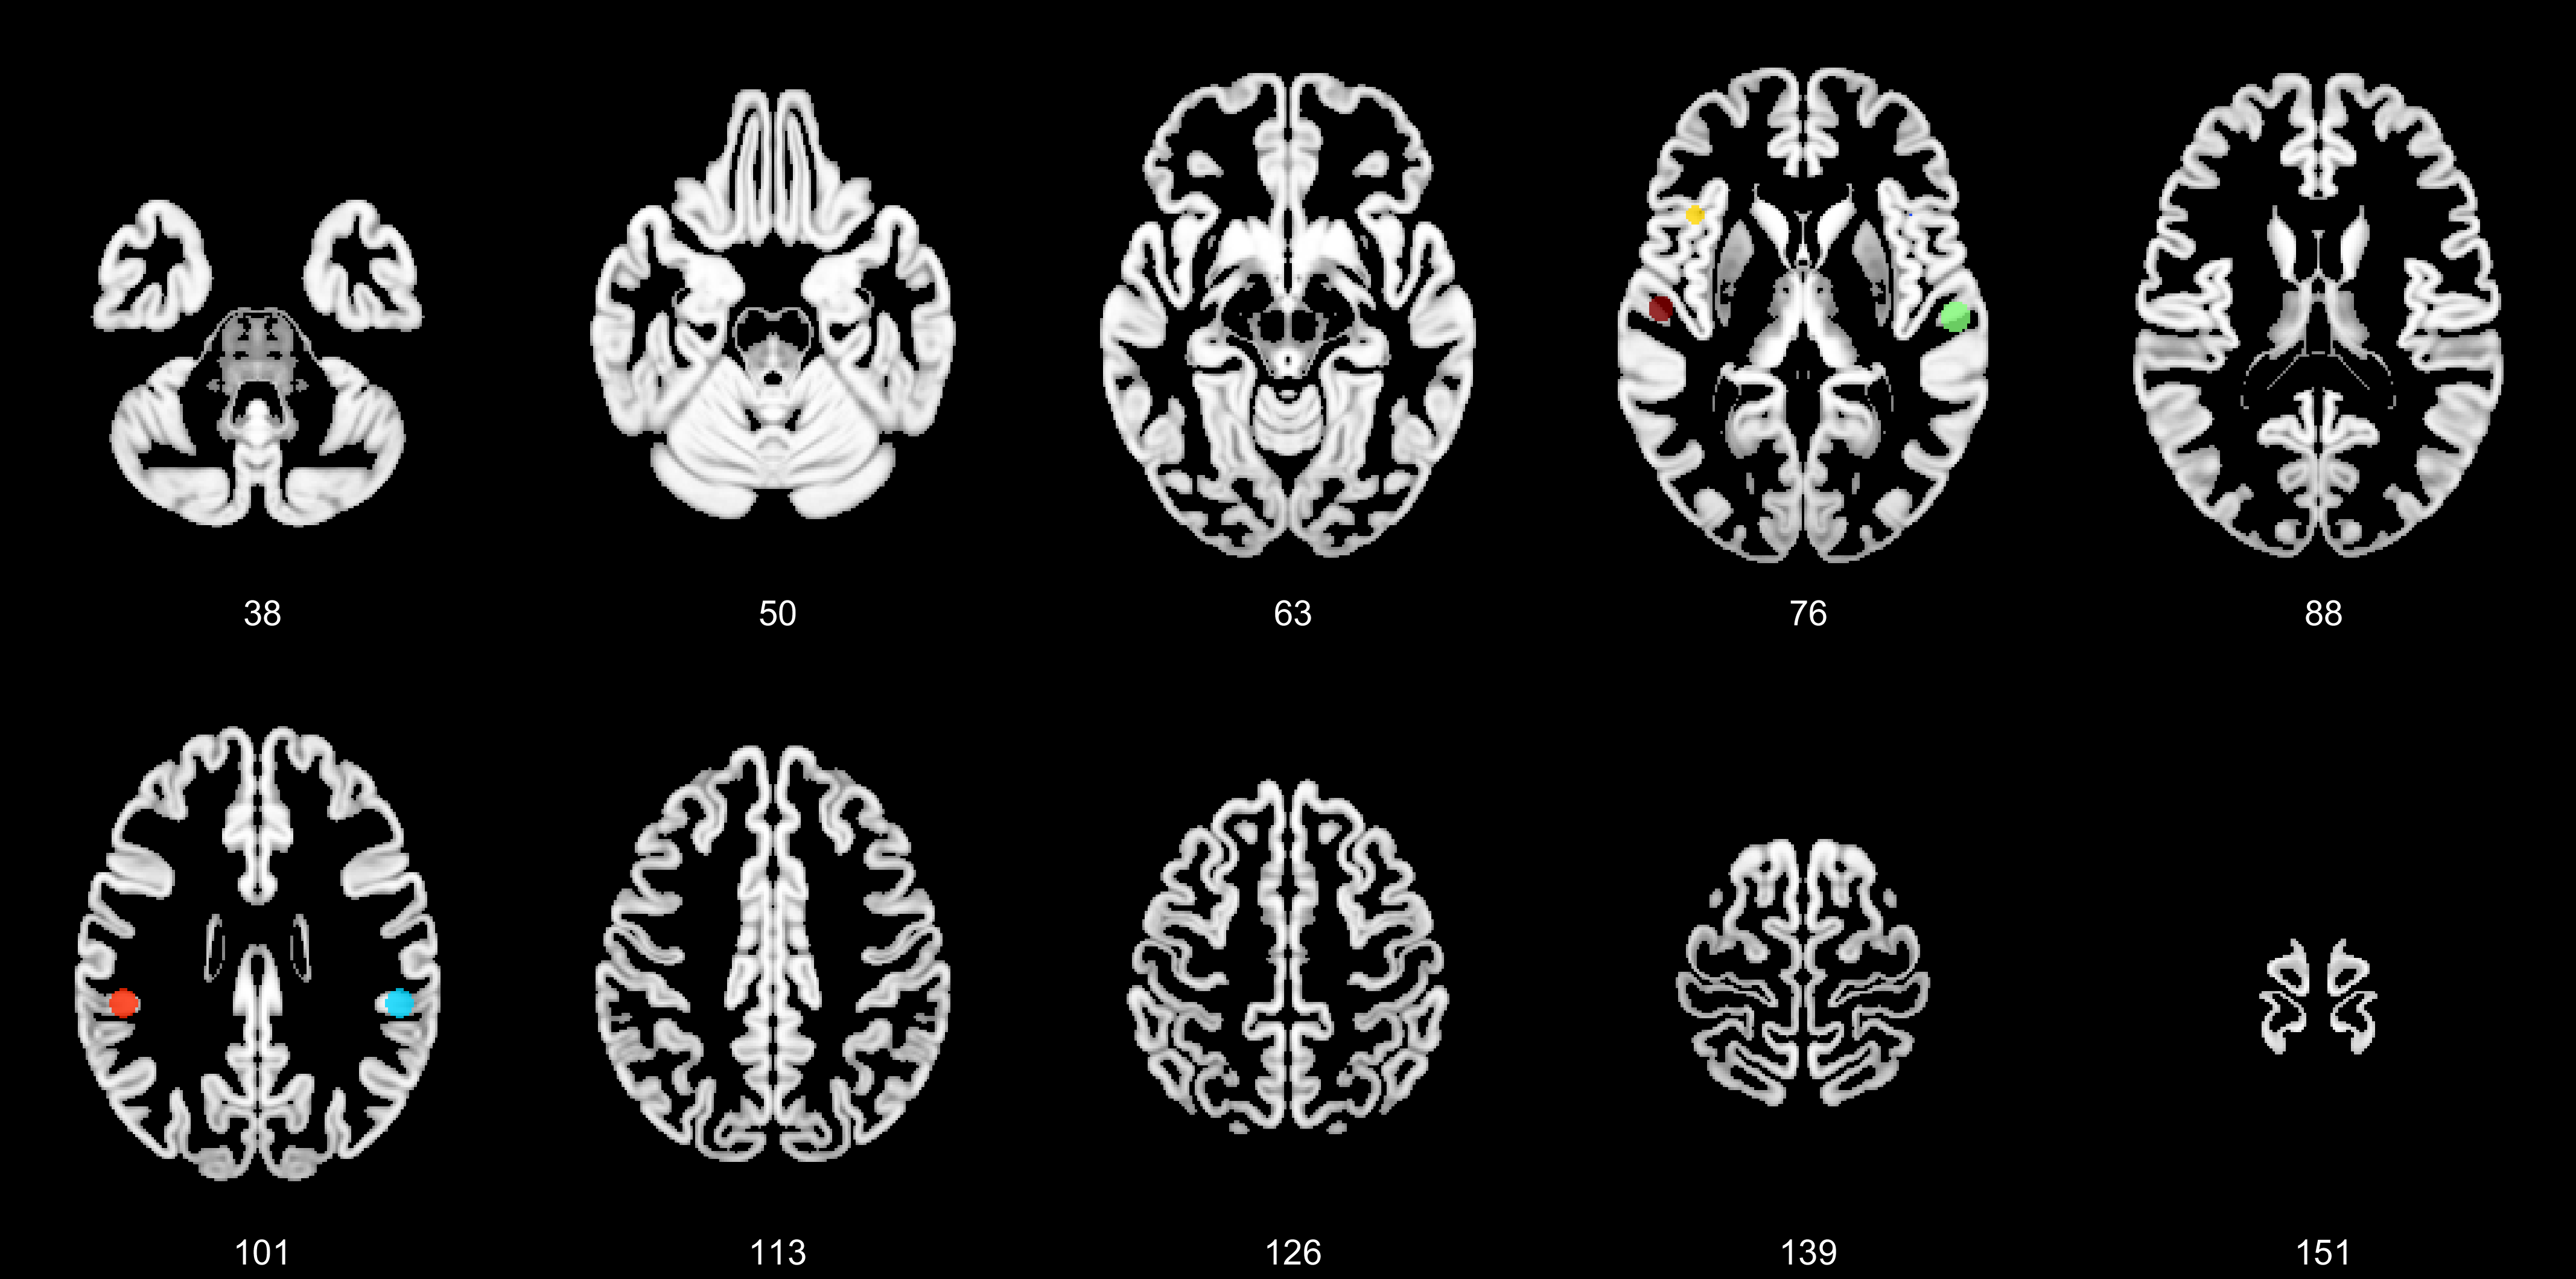

A 3 D Active Contour Method For Automated Segmentation Of The Left

Three Dimensional Gpu Accelerated Active Contours For Automated